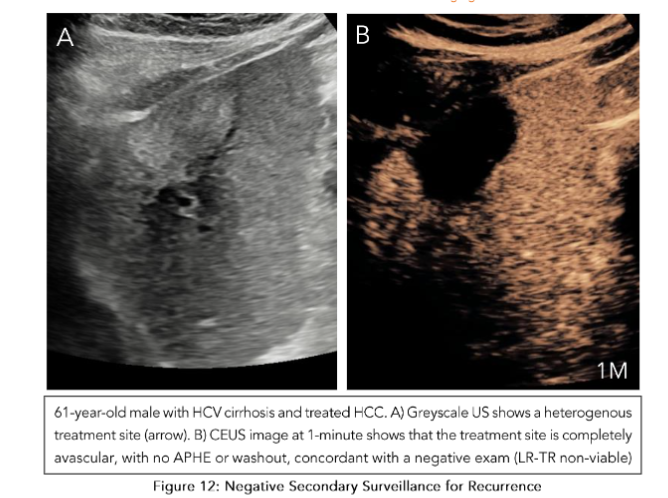

The observations in the secondary surveillance period follow the CEUS LI-RADS treatment response algorithm (TRA)(52). In a technically adequate exam, the ablation site is assessed for both intralesional and perilesional tumor viability. For intralesional viability, if there is no enhancement within the ablation bed, it indicates the absence of a viable tumor. Uncertain viability is characterized by arterial phase hyperenhancement (with or without washout), while hyperenhancement or isoenhancement (with or without washout) suggests the presence of a viable tumor (Figure 10). For perilesional viability, absent viability is characterized by homogeneous enhancement of the ablation margins compared to the rest of the liver. Uncertain viability is characterized by arterial phase hyperenhancement without washout, isoenhancement with washout, or hypoenhancement. The presence of a viable tumor is confirmed by hyperenhancement with washout (Figure 11). Once both these categories are assessed, an overall treatment response score is determined based on their respective contributions. If there is any intralesional or perilesional viability, the overall treatment response score is LI-TR viable. If there is any uncertainty in one without viability present in the other, the overall treatment response score is LR-TR equivocal. Here, an alternative imaging modality like MRI would be useful in clarifying the viability. Only when there is absent viability in both intralesional and perilesional viability is the final category designated as LR-TR nonviable (Figure 12).

Figure 12: Negative Secondary Surveillance for Recurrence